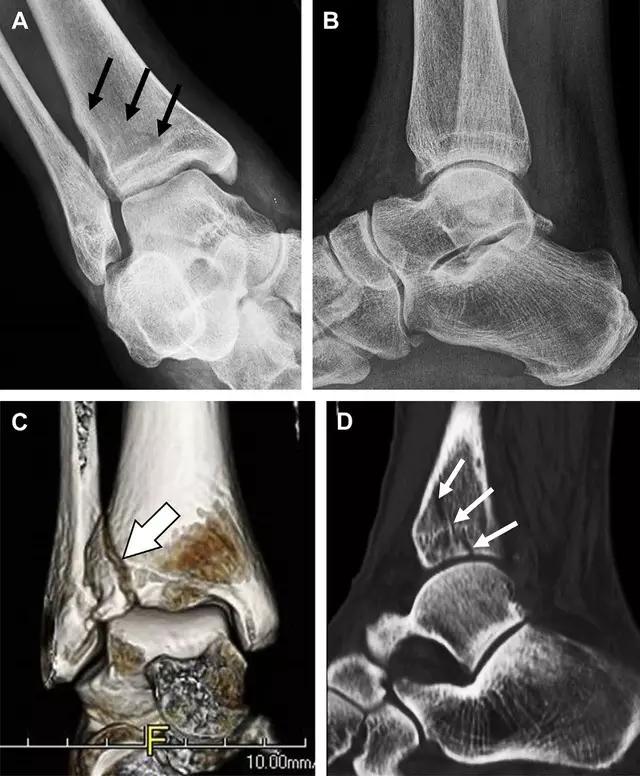

2. Tillaux 骨折

胫骨结节骨折,是足外旋外展时,胫腓前韧带牵拉引起的一种胫骨结节撕脱性骨折。斜位片上可见典型表现。

摔倒后胫骨结节骨折。A 正位片示一细小斜型骨折线(箭头);B 侧位片示正常;C 冠状位 CT 三维成像更清晰地显示了骨折线和骨折块大小(空箭头);D 矢状位 CT 多维重建图像示骨折位置(箭头)(来源:Radiol Clin N Am 53 (2015) 737–755,YU,Ohio)